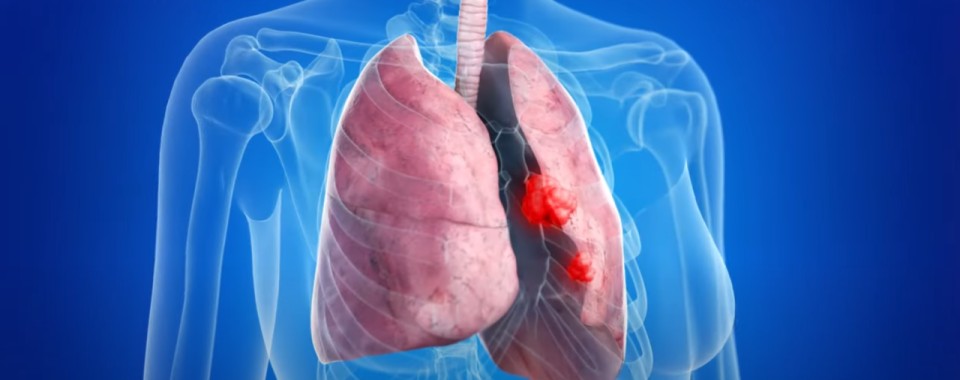

폐암 초기증상

어깨 및 팔 통증

- 설명: 폐의 꼭대기 부위에 암이 생기면 어깨나 팔로 가는 신경을 압박해 통증을 유발할 수 있습니다.

두통, 어지럼증

- 설명: 폐암이 뇌로 전이되거나 상체로 가는 혈관을 막으면 두통, 어지럼증, 혹은 팔다리 마비와 같은 신경학적 증상이 나타날 수 있습니다.

폐암 초기증상 목이나 얼굴의 부종

- 설명: 폐암이 목의 림프절을 막거나, 상체에서 심장으로 혈액을 운반하는 상대정맥을 압박하면 목이나 얼굴이 붓는 증상이 나타날 수 있습니다.